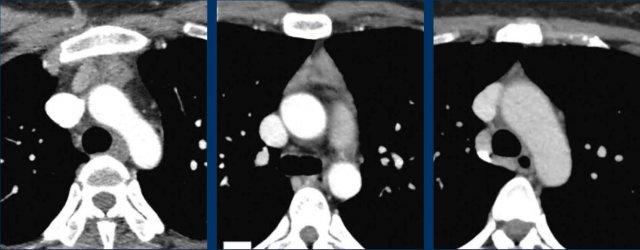

Ở trẻ sơ sinh, tuyến ức có thể khá lớn, đặc biệt khi có suy hô hấp, và có thể biểu hiện trên X-quang ngực với dấu hiệu cánh buồm (mũi tên đen).

Dấu hiệu cánh buồm tuyến ức là một phát hiện bình thường ở trẻ nhũ nhi và không nên nhầm lẫn với dấu hiệu cánh buồm thuyền, trong đó thùy tuyến ức bị đẩy ra ngoài và lên trên do tràn khí trung thất (mũi tên trắng).